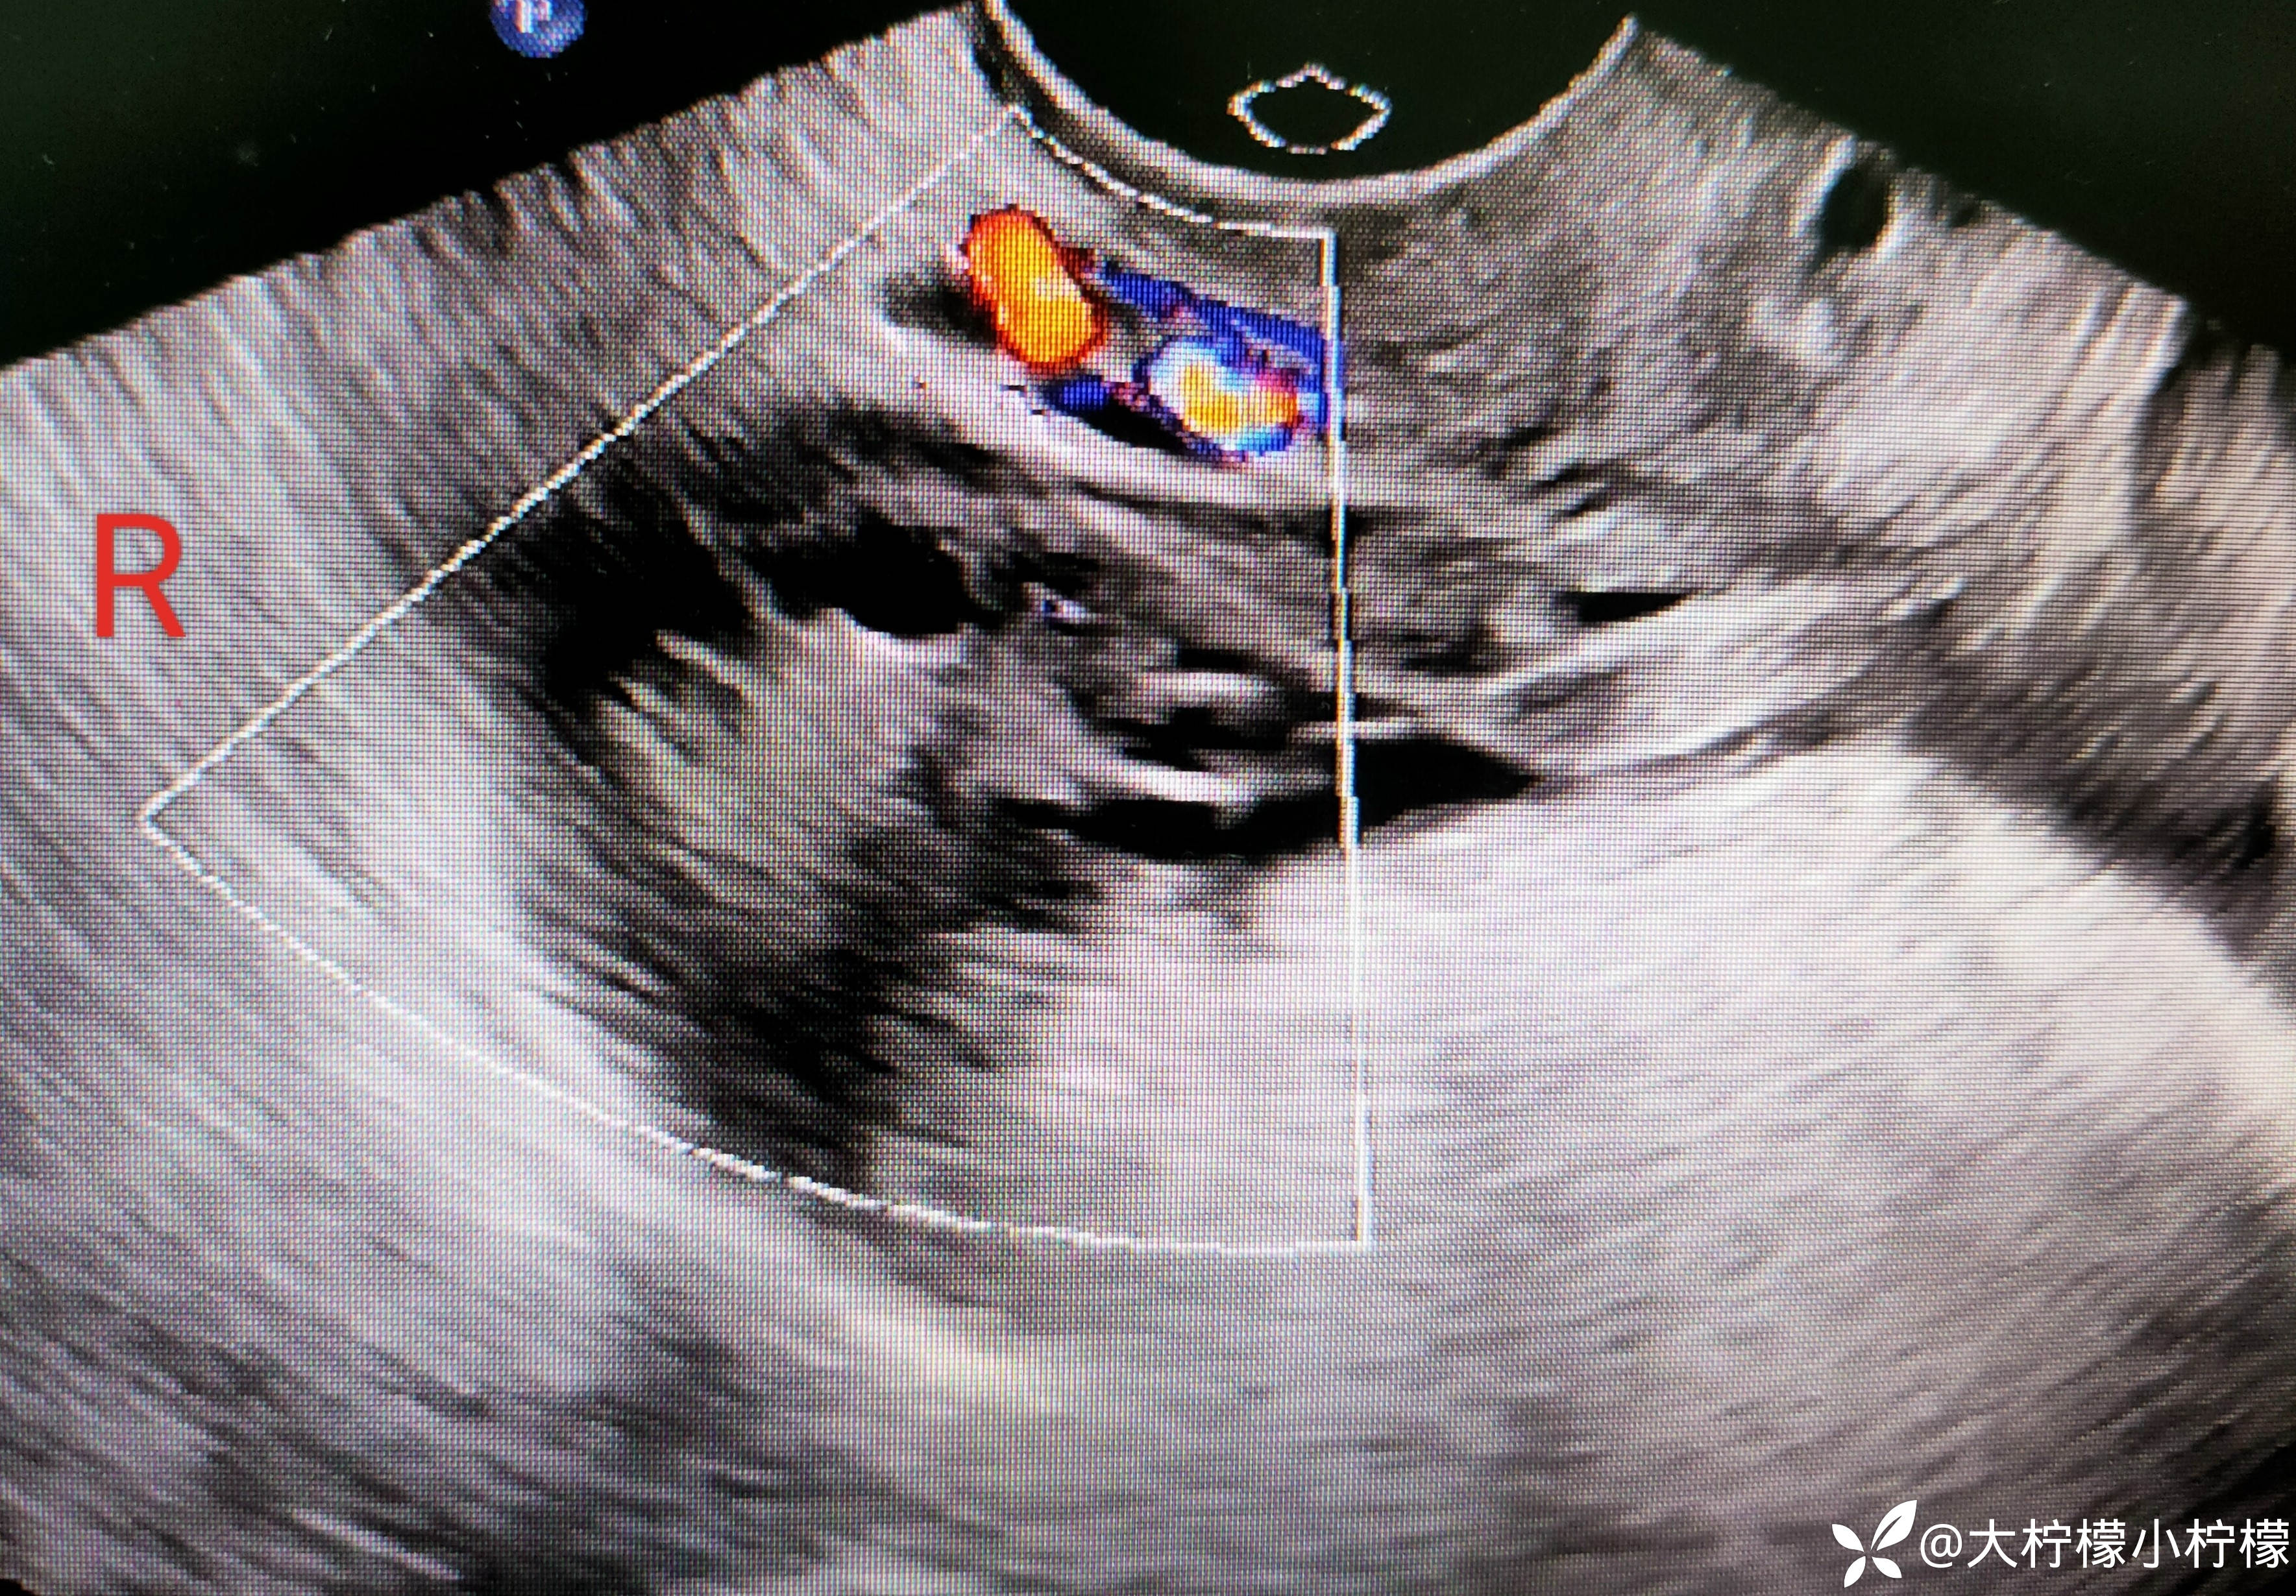

简要病史:患者年轻女性,平素月经周期规律,6-7/30余天,末次月经2023年10月16日,月经量正常,有痛经史,8小时前同房后出现左侧下腹部疼痛,呈持续,急诊超声:如下:

左附件区不均质回声,卵巢被包裹在内。